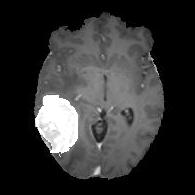

We argue that the sub-optimal paradigm of processing different abstractions within a single CNN pipeline can be remedied through the effective processing of information in a structured manner. Consequently, we devise strategies for disentangling the edge and texture information within a single training pipeline. Figure 2 illustrates how our proposed module, dubbed EG-CNN, can be paired with any existing CNN encoder-decoder to improve segmentation quality near intensity edges. We have applied our EG-CNN to the tasks of brain and liver tumor segmentation in medical images (Figure 3).

(1) Brain MR (2) Liver MR (3) Liver CT (4) Lung CT